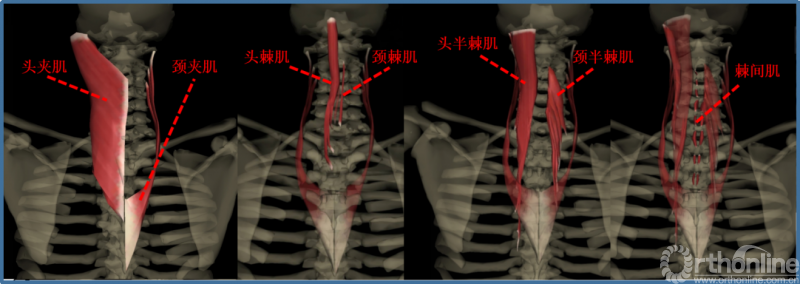

肌肉:

①项背肌分为两层:浅层为斜方肌、菱形肌。深层是颈背部固有肌,长肌在外,短肌在内,共分四层:夹肌、竖脊肌、横突棘肌、枕下肌、横突间肌和棘间肌。

②伸肌装置(中下颈椎)包括斜方肌、夹肌、竖脊肌中的头棘肌和颈棘肌、横突棘肌中颈半棘肌和头半棘肌、棘间肌。附着于棘突及椎板上的颈半棘肌、多裂肌是维持颈椎生理前凸的主要姿势肌群,而以头半棘肌为主的颈伸肌群又是维持颈椎动态稳定的主要因素。